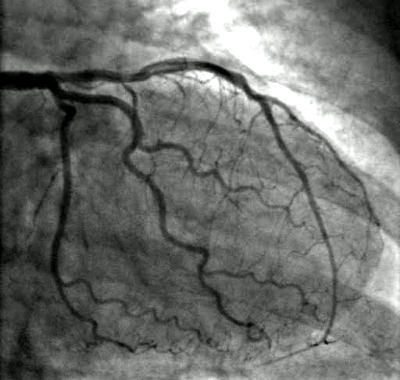

An angiogram is an fascinating procedure. They

used to stick a catheter up from a patient’s groin area and position it near the heart. Now they are able to go in through the wrist. I was able to view a video of them pulsing an opaque dye into her arteries and actually saw the blockage which the cardiologist estimated at 80%. That was the BEFORE. They had installed a stent after blowing up a balloon in her artery to stretch it open and the AFTER image showed the same vessel completely open. Technology is amazing!

Image courtesy of HeartValveSurgery.com